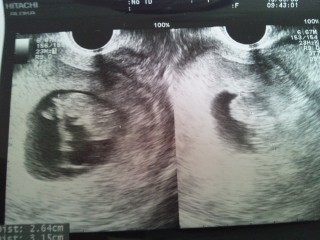

双子ちゃん判定をもらった時のエコーです。 3.15㎝と2.64㎝次は、動いてる所を見てみたいです。